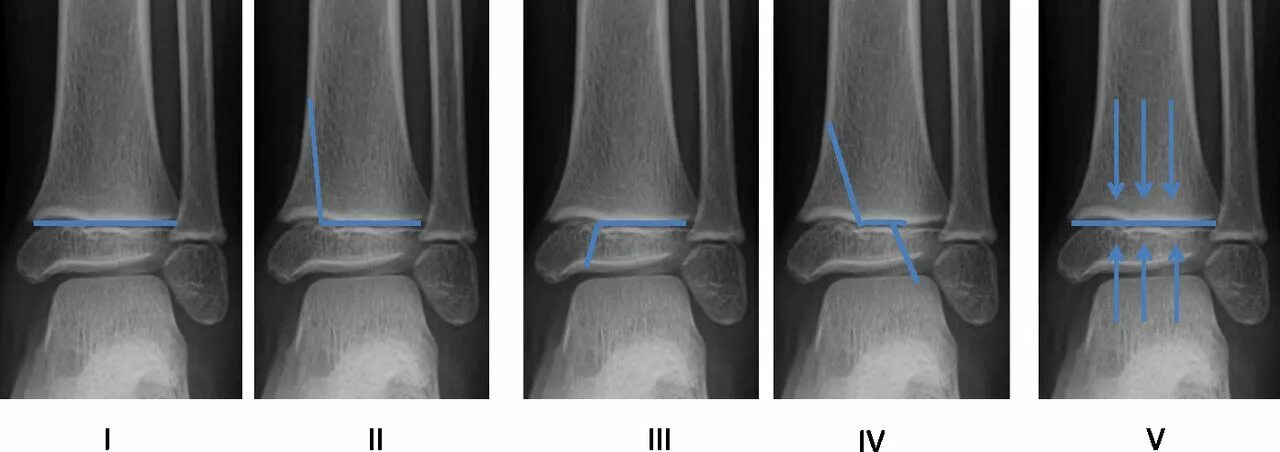

Дисторсия коленного